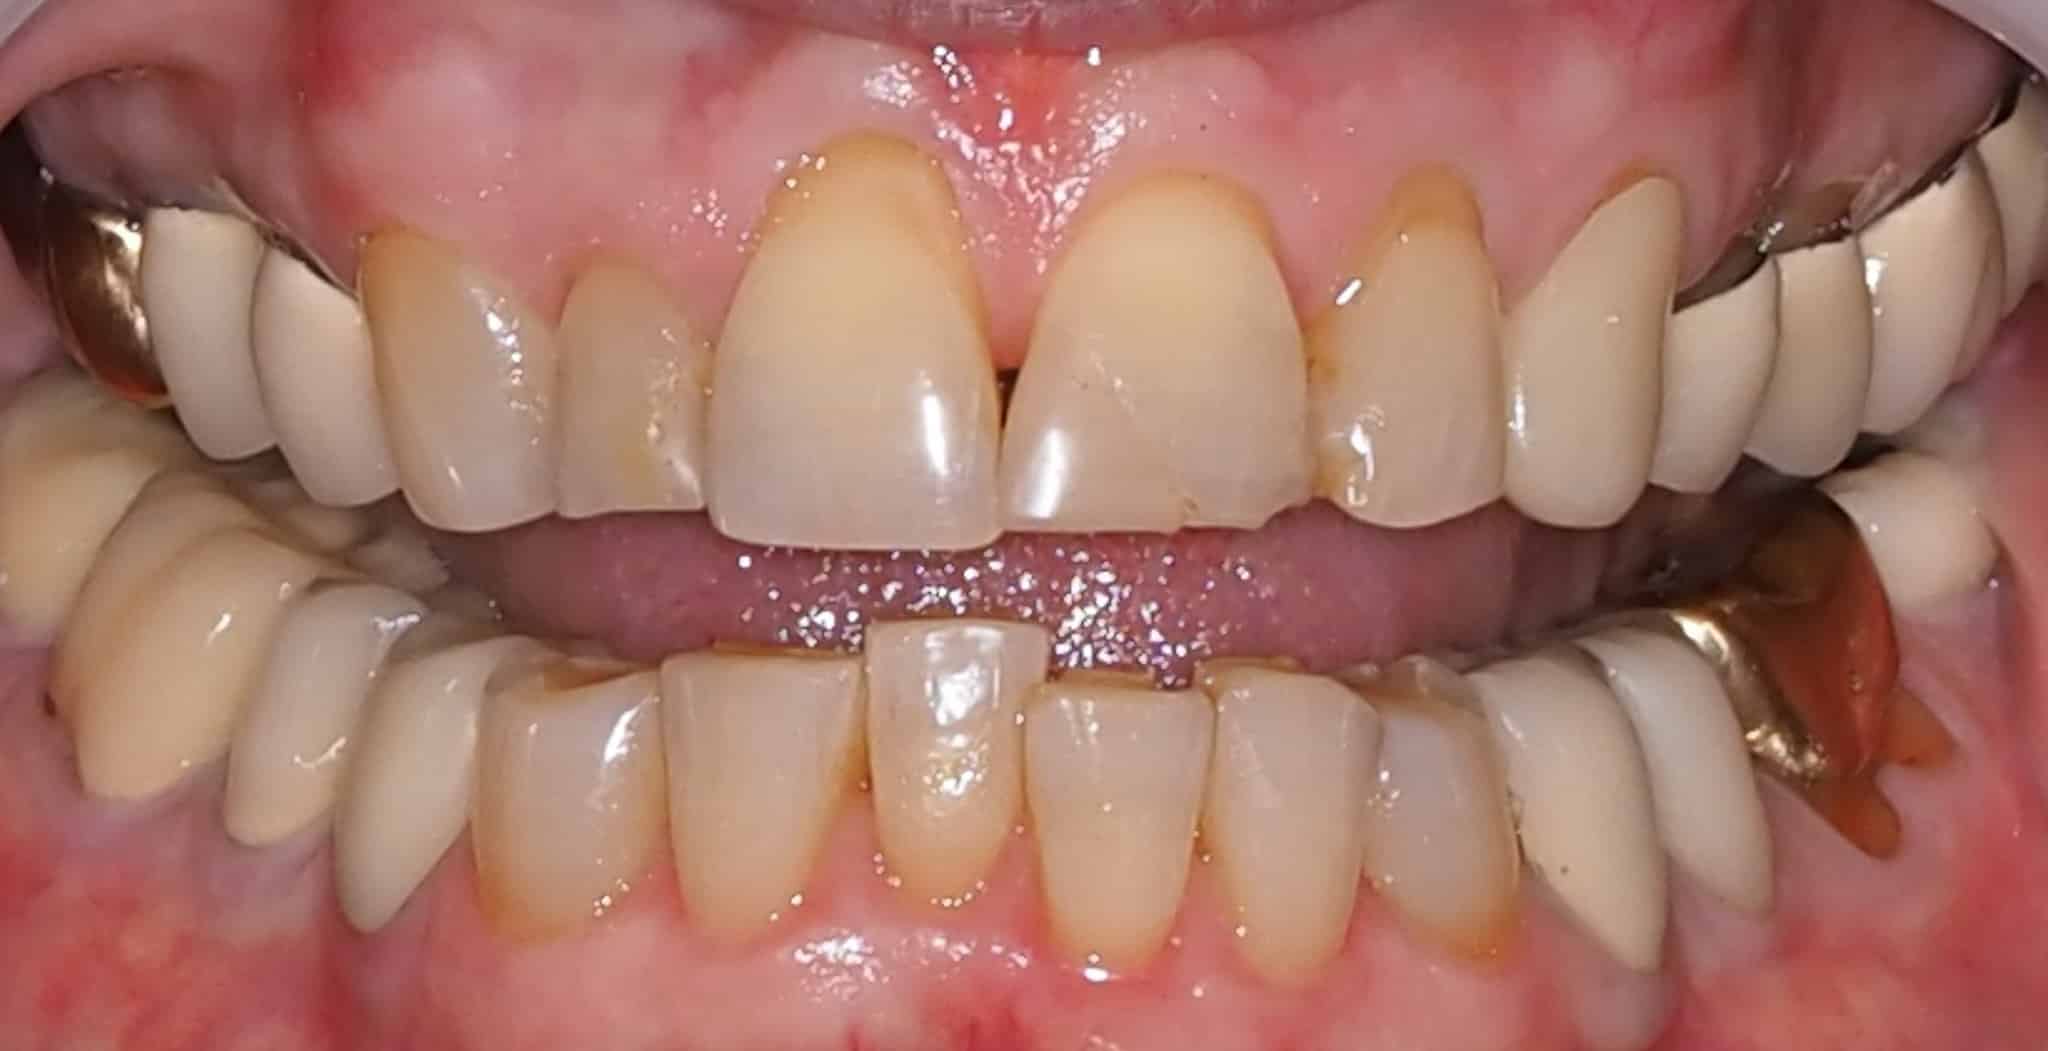

Before and After Image Gallery